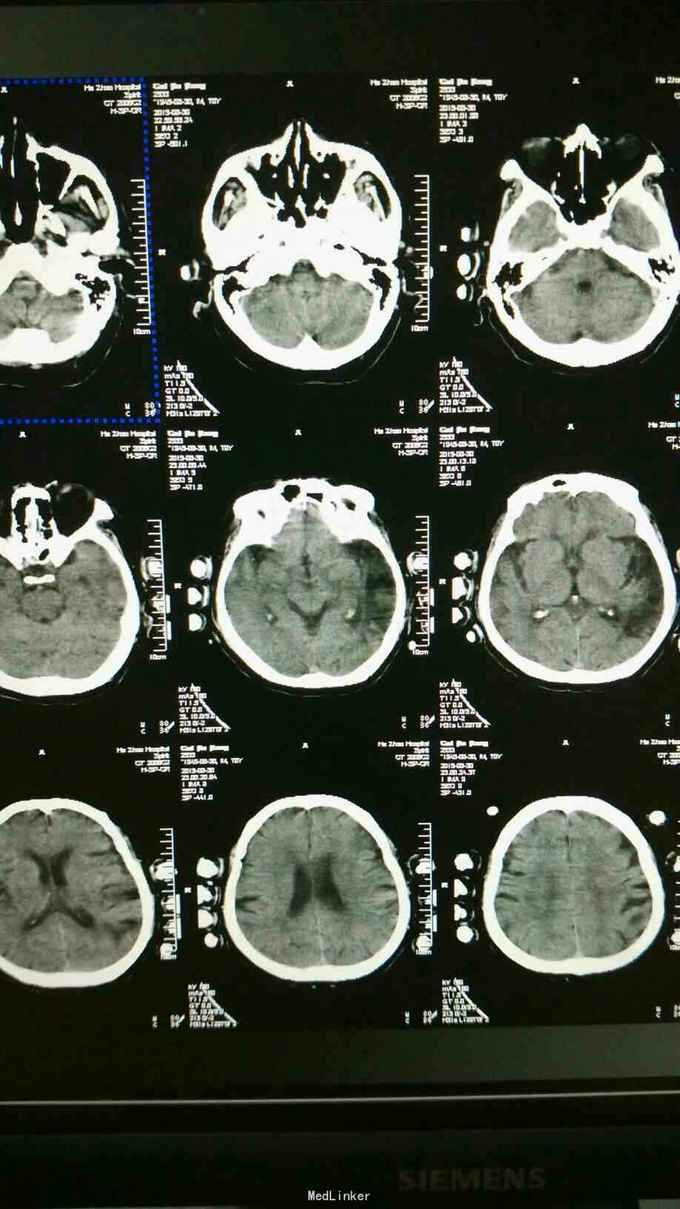

患者男70岁,主因左侧肢体无力,食欲不振两天来诊,既往高血压15年,脑梗死病史一年,有高血压家族史!

入院后查体血压高,反应迟钝,给予脑ct检查,左侧颞叶陈旧性脑梗死,右侧脑室旁腔隙性脑梗死,遂按脑梗死治疗,输液两天后晚上患者突然感觉病情加重,立即给于脑ct检查,跟入院无差别。检查结束后患者突然出现抽搐,全身强直,五分钟后好转,全身大汗。

陈旧性脑梗死,癫痫发作。给予营养脑神经治疗。